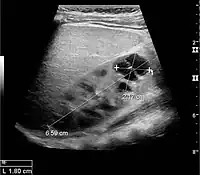

Figure 1. Normal adult kidney. Measurement of kidney length on the US image is illustrated by ‘+’ and a dashed line. *Column of Bertin; ** pyramid; *** cortex; **** sinus.[1]

The length of the adult kidney is normally 10–12 cm, and the right kidney is often slightly longer than the left kidney. The adult kidney size is variable due to the correlation with body height and age; however, normograms for pediatric kidney size are available.[1]

Cortical thickness should be estimated from the base of the pyramid and is generally 7–10 mm. If the pyramids are difficult to differentiate, the parenchymal thickness can be measured instead and should be 15–20 mm (Figure 3). The echogenicity of the cortex decreases with age and is less echogenic than or equal to the liver and spleen at the same depth in individuals older than six months. In neonates and children up to six months of age, the cortex is more echogenic than the liver and spleen when compared at the same depth.[1]